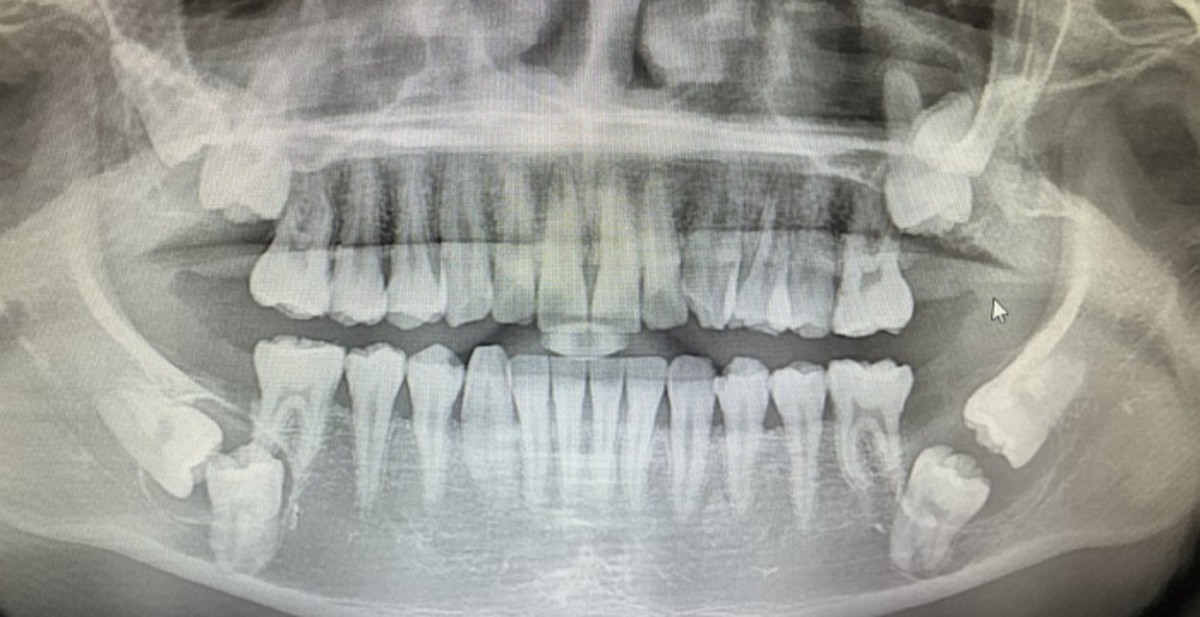

인사이트A씨의 사랑니 / 온라인 커뮤니티

[인사이트] 임우섭 기자 = 입속 치아 중 무려 8개의 치아가 매복돼 있는 사진이 나타나 충격을 주고 있다.

글에 따르면 작성자 A씨는 앞서 지난해 동네 치과에서 진찰을 받았다. 당시 치과 엑스레이 사진에서 치아 8개가 매복돼 있는 것을 발견했는데 치과의사는 작은 곳보다는 큰 병원에서 진찰을 받아야 할 것 같다며 대학병원을 추천했다.

대학병원 내에서 A씨 치아에 대해 진찰한 결과는 꽤 심각했다. 매복된 치아 중 4개는 사랑니이며 나머지 4개는 어금니였기 때문이다.

특히 잇몸 내 신경들이 다 눌려있는 상태로, 의사는 일부 이빨을 뽑게 될 시 구멍이 뚫릴 것이라고 말했다. 또 왼쪽 아래 한 부위는 염증이 아닌 물혹이라고 설명했다.